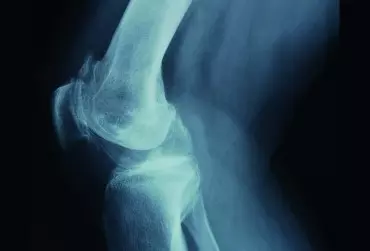

Ograniczenia ruchomości stawu kolanowego

Chcesz wiedzieć więcej? Artykuł "Ból w kolanach przy zginaniu – przyczyny i leczenie" zawiera wartościowe informacje. Ćwiczenie 1. Mobilizacja kości piszczelowej dystalnie – trakcja Cel: Poprawa zakresu ruchomości stawu kolanowego, przygotowanie do mobilizacji ślizgowych, zmniejszenie dolegliwości bólowych, rozluźnienie struktur okołostawowych. Pozycja wyjściowa: Dziecko znajduje się w pozycji leżenia przodem. Staw kolanowy ustawiony jest w pozycji spoczynkowej (20–30° zgięcia) lub w aktualnie maksymalnym zakresie ruchu. Dystalny koniec kości udowej ustabilizowany na stole terapeutycznym pasem stabilizacyjnym. Obie dłonie terapeuty obejmują podudzie dziecka w okolicy kostek z obu stron i stabilizują stopę przy ciele terapeuty. Terapeuta może przy wykonaniu tej techniki skorzystać z pasa trakcyjnego, który jest przełożony przez tułów oraz obie jego dłonie. Sposób wykonania ćwiczenia: Poprzez delikatne przeniesienie swojego ciężaru na nogę zakroczną terapeuta odchyla się nieznacznie do tyłu, co spowoduje separację powierzchni stawowych. Kierunek ruchu: Kość piszczelowa – dystalnie (trakcja). Liczba powtórzeń: 3 × od 7 sekund do 1,5 minuty. Oczekiwany efekt: Poprawa zakresów ruchomości w stawie kolanowym, zmniejszenie dolegliwości bólowych, rozluźnienie struktur i tkanek okołostawowych. Ćwiczenie 2.  Mobilizacja ślizgu brzusznego kości piszczelowej Cel: Odtworzenie ślizgu brzusznego kości piszczelowej względem kości udowej dla poprawy wyprostu stawu kolanowego. Pozycja wyjściowa: Dziecko znajduje się w pozycji leżenia przodem, a jego podudzie oraz rzepka wystają poza krawędź leżanki. Terapeuta stoi zwrócony w kierunku strony przyśrodkowej podudzia dziecka. Dystalna część uda stabilizowana jest pasem stabilizacyjnym na stole. Lewa dłoń terapeuty obejmuje od strony grzbietowej dystalną część podudzia dziecka i przytrzymuje ją przy swoim ciele. Prawa dłoń terapeuty również od strony grzbietowej obejmuje dystalnie od szpary stawowej boczną, proksymalną część podudzia dziecka. Terapeuta w tej pozycji obniża delikatnie ciężar swojego ciała, uginając nieznacznie stawy kolanowe. Kierunek ruchu: Kość piszczelowa – dobrzusznie. Zastosowanie: Przy ograniczonym ruchu wyprostu w stawie kolanowym. Podczas terapii przyśrodkowej części stawu terapeuta stoi zwrócony w kierunku bocznej strony podudzia, obejmując proksymalną, przyśrodkową część. Przyśrodkowa i boczna część stawu muszą być w tym przypadku leczone oddzielnie. Szczególnie istotne jest to, aby podczas mobilizacji unikać komponenty toczenia w stawie, ponieważ może to doprowadzić do kompresji powierzchni stawowych i spowodować nasilenie dolegliwości bólowych. Mobilizację można stosować w submaksymalnym zakresie wyprostu w stawie kolanowym. Liczba powtórzeń: 3 × od 7 sekund do 1,5 minuty. Oczekiwany efekt: Poprawa zakresu ruchu wyprostu w stawie kolanowym. Ćwiczenie 3.  Mobilizacja ślizgu grzbietowego kości piszczelowej Cel: Odtworzenie ślizgu grzbietowego kości piszczelowej względem kości udowej dla poprawy ruchu zgięcia w stawie kolanowym. Pozycja wyjściowa: Dziecko znajduje się w pozycji leżenia tyłem, a jego podudzie wystaje poza krawędź stołu. Terapeuta stoi zwrócony w kierunku przyśrodkowej strony podudzia dziecka. Dystalna część uda dziecka ustabilizowana na stole. Lewa dłoń terapeuty obejmuje dystalną część podudzia dziecka od strony brzusznej i stabilizuje ją przy ciele. Prawa dłoń terapeuty obejmuje proksymalnie boczną część podudzia dziecka, dystalnie od szpary stawowej. Kierunek ruchu: Podudzie – dogrzbietowo. Zastosowanie: W przypadku ograniczenia ruchu zginania w stawie kolanowym. Podczas terapii przedziału przyśrodkowego stawu kolanowego terapeuta stoi zwrócony w kierunku bocznej strony podudzia dziecka, obejmując jego proksymalną, przyśrodkową część. Zarówno przyśrodkowy, jak i boczny przedział stawu kolanowego muszą być w tym przypadku leczone oddzielnie. Szczególnie istotne jest to, aby podczas mobilizacji unikać komponenty toczenia w stawie, ponieważ może to doprowadzić do kompresji powierzchni stawowych i spowodować nasilenie dolegliwości bólowych. Mobilizację można stosować w submaksymalnym zakresie zgięcia w stawie kolanowym. Liczba powtórzeń: 3 × od 7 sekund do 1,5 minuty. Oczekiwany efekt: Poprawa zakresu ruchu zgięcia w stawie kolanowym. Ćwiczenie 4.  Mobilizacja ślizgu dobocznego kości piszczelowej Cel: Odtworzenie ślizgu dobocznego kości piszczelowej względem kości udowej. Pozycja wyjściowa: Dziecko znajduje się w pozycji leżenia na boku na stole terapeutycznym. Jego podudzie wystaje poza krawędź stołu. Lewa dłoń terapeuty obejmuje od strony przyśrodkowej dystalną część podudzia dziecka i przytrzymuje ją przy ciele. Prawa dłoń terapeuty od strony przyśrodkowej obejmuje proksymalną część podudzia dziecka dystalnie od szpary stawowej. Kierunek ruchu: Kość piszczelowa – dobocznie. Zastosowanie: W przypadku ograniczonego zginania i prostowania w stawie kolanowym oraz deformacji szpotawej stawu kolanowego. Mobilizację można wykonywać w różnym zakresie zgięcia stawu, w zależności od występującego w danej wartości kątowej zgięcia ograniczenia ślizgu dobocznego kości piszczelowej. Liczba powtórzeń: 3 × od 7 sekund do 1,5 minuty. Oczekiwany efekt: Poprawa zakresu ruchomości w stawie kolanowym, poprawa ślizgu bocznego w stawie kolanowym.   Ćwiczenie 5.  Mobilizacja ślizgu przyśrodkowego kości piszczelowej Cel: Odtworzenie ślizgu przyśrodkowego kości piszczelowej względem kości udowej. Pozycja wyjściowa: Dziecko znajduje się w pozycji leżenia na boku na stole terapeutycznym. Jego podudzie wystaje poza krawędź stołu. Terapeuta chwyta swoją lewą dłonią dystalną część podudzia od strony bocznej i podtrzymuje ją przy ciele. Prawa dłoń chwyta proksymalną część podudzia dziecka od strony bocznej dystalnie, bezpośrednio za szparą stawową. Kierunek ruchu: Kość piszczelowa – przyśrodkowo. Zastosowanie: W przypadku ograniczonego zginania i prostowania w stawie kolanowym oraz w leczeniu deformacji koślawej stawu kolanowego. Mobilizację można wykonywać w różnym zakresie zgięcia stawu, w zależności od występującego w danej wartości kątowej zgięcia ograniczenia ślizgu przyśrodkowego kości piszczelowej. Liczba powtórzeń: 3 × od 7 sekund do 1,5 minuty. Oczekiwany efekt: Poprawa zakresu ruchomości w stawie kolanowym, poprawa ślizgu przyśrodkowego w stawie kolanowym. Ćwiczenie 6.  Technika mobilizacji z ruchem MWM (mobilisation with movement) według Mulligana dla poprawy wyprostu stawu kolanowego i/lub zmniejszenia bólu podczas  ruchu wyprostu Cel: Poprawa zakresu ruchu wyprostu stawu kolanowego. Pozycja wyjściowa: Dziecko znajduje się w pozycji leżenia tyłem na stole terapeutycznym. Terapeuta staje z boku leżanki od strony leczonej kończyny dolnej. Staw kolanowy dziecka znajduje się w zgięciu ok. 20–30°. Pas mobilizacyjny przełożony jest od strony tylnej na proksymalnym końcu podudzia dziecka, dystalnie od szpary stawowej stawu kolanowego, naciągnięty na plecach terapeuty w taki sposób, aby wektor siły mobilizacyjnej przebiegał równolegle do wklęsłej powierzchni stawowej na kości piszczelowej. Lewa ręka terapeuty obejmuje od strony brzusznej dystalny koniec podudzia dziecka, podczas gdy prawa ręka stabilizuje udo w części dystalnej (rys. A). Sposób wykonania ćwiczenia: Terapeuta stosuje korekcyjny ślizg brzuszny kości piszczelowej względem kości udowej poprzez napięcie pasa i prosi o wykonanie czynnego ruchu wyprostu stawu kolanowego, obserwując, czy podczas wykonywania ruchu pojawiają się dolegliwości bólowe (rys. B). Jeżeli podczas wykonania czynnego ruchu wyprostu z korekcją nie pojawi się ból, terapeuta może kontynuować technikę, utrzymując korekcyjny ślizg przez cały czas jej trwania. Jeżeli pomimo zastosowanego ślizgu korekcyjnego nadal pojawia się ból, nie należy wykonywać kolejnych powtórzeń. Liczba powtórzeń: 3 × od 8 do 10 powtórzeń. Oczekiwany efekt: Poprawa zakresu ruchu wyprostu w stawie kolanowym, zmniejszenie dolegliwości bólowych występujących podczas ruchu wyprostu w stawie kolanowym. Ćwiczenie 7. Technika mobilizacji z ruchem MWM według Mulligana dla poprawy zgięcia stawu kolanowego (1) Cel: Poprawa zakresu ruchu zgięcia stawu kolanowego. Pozycja wyjściowa: Dziecko znajduje się w pozycji leżenia przodem. Terapeuta staje z boku leżanki po przeciwnej stronie do leczonej kończyny dolnej. Staw kolanowy znajduje się w zgięciu ok. 90°. Pas mobilizacyjny przełożony jest od strony bocznej leczonego stawu kolanowego na proksymalnym końcu podudzia dziecka, tuż za szparą stawową. Pas rozciągnięty jest na biodrach terapeuty w taki sposób, aby wektor siły mobilizacyjnej przebiegał równolegle do wklęsłej powierzchni stawowej na kości piszczelowej.  Prawa ręka terapeuty ułożona jest na dystalnej części kości udowej i stabilizuje ją od strony przyśrodkowej, podczas gdy lewa ręka obejmuje dystalną części podudzia. Sposób wykonania ćwiczenia: Terapeuta stosuje korekcyjny ślizg przyśrodkowy kości piszczelowej względem kości udowej poprzez napięcie pasa, odchylając swój tułów i miednicę do tyłu. Następnie prosi o wykonanie czynnego ruchu zgięcia stawu kolanowego, obserwując, czy podczas wykonywania ruchu pojawiają się dolegliwości bólowe. Jeżeli podczas wykonania czynnego ruchu zgięcia z korekcją nie pojawi się ból, terapeuta może kontynuować technikę, utrzymując korekcyjny ślizg przez cały czas jej trwania. Technika może być również szczególnie przydatna w przypadku leczenia dzieci z deformacją szpotawą stawu kolanowego. W analogiczny sposób można wykonywać korekcyjny ślizg boczny, odpowiednio zmieniając chwyt. Terapeuta w takim przypadku staje z boku leżanki po stronie leczonej kończyny. Technika z korekcyjnym ślizgiem bocznym jest szczególnie przydatna u dzieci z deformacją koślawą stawu kolanowego. Jeżeli pomimo zastosowanego ślizgu korekcyjnego nadal pojawia się ból, nie należy wykonywać kolejnych powtórzeń. Liczba powtórzeń: 3 × od 8 do 10 powtórzeń. Oczekiwany efekt: Poprawa zakresu ruchu zgięcia w stawie kolanowym, zmniejszenie dolegliwości bólowych występujących podczas ruchu zgięcia w stawie kolanowym, poprawa ograniczonego ślizgu bocznego/przyśrodkowego w stawie kolanowym. Ćwiczenie 8.  Technika mobilizacji z ruchem MWM według Mulligana dla poprawy zgięcia stawu kolanowego (2) Cel: Poprawa zakresu ruchu zgięcia stawu kolanowego. Pozycja wyjściowa: Dziecko znajduje się w pozycji leżenia tyłem. Terapeuta staje z boku leżanki od strony leczonej kończyny dolnej. Staw kolanowy znajduje się w zgięciu ok. 90°. Terapeuta prawą ręką obejmuje od strony brzusznej dystalny koniec kości udowej, a nasadę lewej dłoni przykłada w okolicę guzowatości piszczelowej w taki sposób, aby wektor siły mobilizacyjnej przebiegał równolegle do wklęsłej powierzchni stawowej na kości piszczelowej. Sposób wykonania ćwiczenia: Terapeuta stosuje korekcyjny ślizg grzbietowy kości piszczelowej względem kości udowej poprzez wywieranie nacisku nasadą dłoni na guzowatość kości piszczelowej. Następnie prosi o wykonanie czynnego ruchu zgięcia stawu kolanowego, obserwując, czy podczas wykonywania ruchu pojawiają się dolegliwości bólowe. Jeżeli podczas wykonania czynnego ruchu zgięcia z korekcją nie pojawi się ból, terapeuta może kontynuować technikę, utrzymując korekcyjny ślizg przez cały czas jej trwania. Należy pamiętać, że płaszczyzna wklęsłej powierzchni stawowej kości piszczelowej podczas ruchu zmienia się, dlatego lewe przedramię terapeuty również powinno zmieniać swoje ułożenie, dostosowując się do aktualnej pozycji stawu. Jeżeli pomimo zastosowanego ślizgu korekcyjnego nadal pojawia się ból, nie należy wykonywać kolejnych powtórzeń. Liczba powtórzeń: 3 × od 8 do 10 powtórzeń. Oczekiwany efekt: Poprawa zakresu ruchu zgięcia w stawie kolanowym, zmniejszenie dolegliwości bólowych występujących podczas ruchu zgięcia w stawie kolanowym.